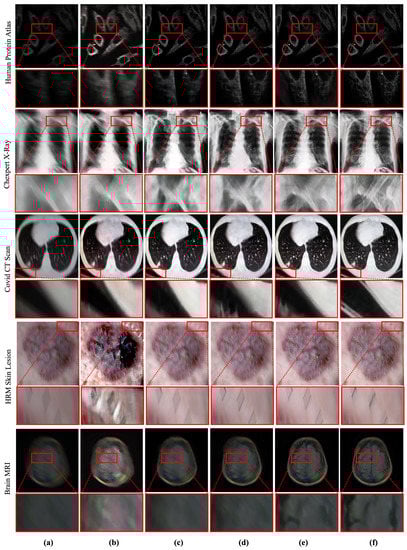

Oppositely, deep learning-based image deblurring techniques have evolved significantly in the past decade [10]. These methods have illustrated significant improvement in removing deblurs in non-medical images. Notably, the deep deblurring methods outperform traditional counterparts by a considerable margin in diverse data samples [10]. To examine the existing deep deblurring techniques for MID, we trained and tested these methods on medical images collected from multiple image modalities, as shown in Figure 1. It has been found that the existing state-of-the-art (SOTA) deep deblurring and MID methods fail to recover texture and salient information from blurry medical images. Moreover, they are prone to produce visually disturbing artifacts while removing blur from the given image.

It is worth noting that medical images are typically captured with different image acquisition mechanisms and comprise more salient features than non-medical images. However, removing blur from medical images has a significant impact. It can substantially accelerate the performance of medical image analysis tasks. Despite a wide range of applications and real-world impacts, the performance of existing MID methods is inadequate. They fail to address the large-kernel blind blurs in medical images, as shown in Figure 1. The limitation of existing methods motivated this study to incorporate a robust learning-based MID solution, which can handle the large kernel blurs without explicitly considering image modality.

Figure 5 depicts the qualitative comparison between deep deblurring methods. It can be seen that the proposed method outperforms the existing deblurring methods by recovering salient details. Apart from recovering details, the proposed network can remove maximum blur without illustrating visually disturbing artifacts. The proposed RD-SAM helps us learn salient features with local-global attention, while removing blind blurs from medical images. Overall, the qualitative comparison verifies the feasibility of the proposed method for MID in real-world applications.

Figure 1. Performance of existing medical image deblurring methods in removing blind motion blur. The existing deblurring methods immensely failed in removing blur from medical images. (a) Blurry input. (b) Result obtained by TEMImageNet [9]. (c) Result obtained by ZhaoNet [11]. (d) Result obtained by Deep Deblur [12]. (e) Result obtained by SRN Deblur [13]. (f) Proposed Method.

Figure 5. Qualitative comparison between deep MID methods. The proposed method outperforms the existing methods by recovering salient information from blurry medical images. (a) Blurry input. (b) Result obtained by TEMImageNet [9]. (c) Result obtained by ZhaoNet [11]. (d) Result obtained by Deep Deblur [12]. (e) Result obtained by SRN Deblur [13]. (f) Proposed Method.